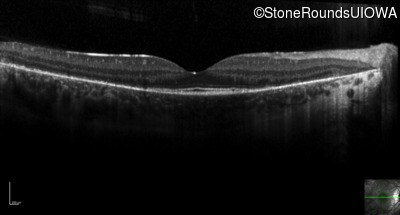

Optical Coherence Tomography - Left - 20/20 sc

Exemplar / OCT Stack

OCT Stack